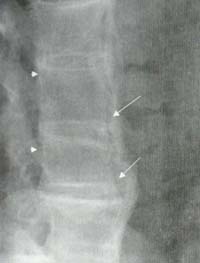

La osteoporosis, erosiones óseas y la anquilosis intraarticular no son hallazgos característicos de esta enfermedad. La osificación del ligamento longitudinal posterior se ha identificado en la región cervical en aproximadamente el 50% de los pacientes. Puede coexistir la espondilitis anquilosante con DISH14 (Figura 15), sin embargo esta asociación es rara y ha sido informada pocas veces en la literatura15.

Figura 15. Espondilitis anquilosante y DISH. Se visualiza rectificación de la lordosis lumbar, osteopenia generalizada, calcificación del ligamento longitudinal anterior, una zona radio-lúcida entre el ligamento y los cuerpos vertebrales (Flechas) además de calcificación del ligamento longitudinal posterior (Cabezas de flechas).